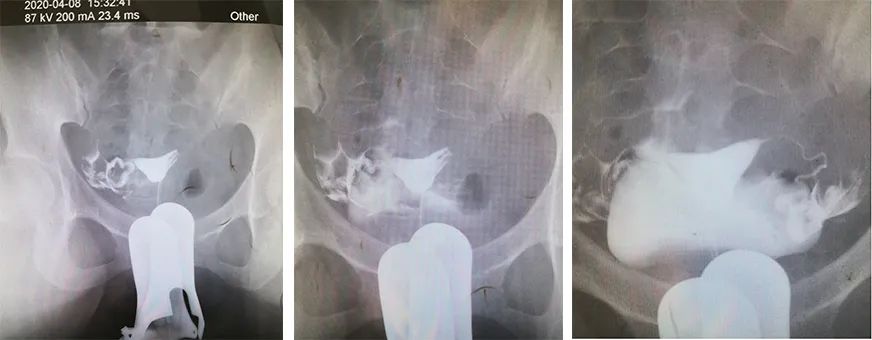

彭女士此前做过输卵管造影,为了分析出她“生化妊娠”的原因,我觉得还是自己读片更保险,而她刚好把原始X摄片带在身边。

这一看,可就看出了问题。

认真读片后,我告知她:其实她的右侧输卵管通畅,左侧输卵管显影延迟(不排除伞端炎症可能),非常容易发生宫外孕或生化妊娠可能!